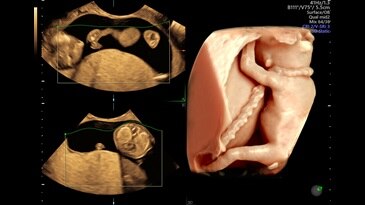

Fetal brain with C2-9 probe and HDRes

Fetus with HDlive™ generated with SonoRenderlive

HDlive Studio on a 10-week fetus